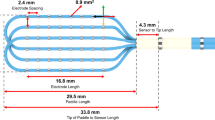

Multielectrode basket catheters were positioned endocardially in both ventricles for mapping and remained in the same position throughout the entire duration of all experiments (Fig. 1 A). These catheters were positioned as deep into the ventricles to permit contact along the complex intracavitary structures and its closely associated and overlapping His-Purkinje tissue. These regions that we refer to as the distal RV and LV are regions that we define as including the complex compartment of these ventricular regions including the RV moderator band, right- and left-sided papillary muscles, false tendons, and the distal Purkinje tissue. The locations of the mapping catheters were confirmed by fluoroscopy: a 38 mm Constellation catheter (Boston Scientific, Marlborough MA—64 electrodes on eight splines) was placed in the distal RV, a 60 mm Constellation catheter (Boston Scientific, Marlborough MA—64 electrodes on eight splines) was positioned in the distal LV, and an Orion catheter (Boston Scientific, Marlborough MA—64 electrodes on eight splines) was positioned in the RVOT (Fig. 1 C). A retrograde aortic approach was used to access the LV in all canines.